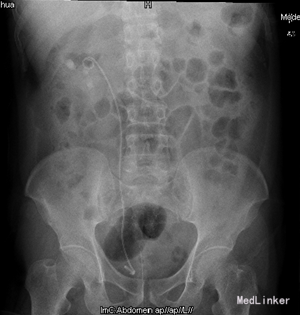

诊断:1、右肾结石 2、右侧输尿管开口囊肿 3、右侧输尿管下段结石 4、右肾囊肿 5、尿路感染 行右肾碎石术,术中见:右侧输尿管开口处一囊肿,约1.0cm×0.8cm,压迫右侧输尿管开口,随输尿管口喷尿时呈隆起行改变,囊肿内发现一大小约0.5×0.2cm大小结石,右肾盂大量沙粒样结石。

术后16天,右肾内结石基本消除,予以拔出支架管,输尿管开口囊肿确实少见,对于这种囊肿,各位老师有没有什么好的办法。